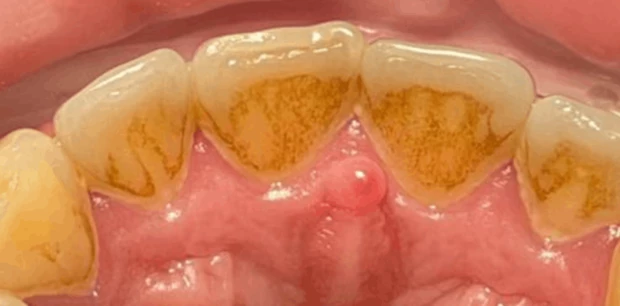

Профгигиена

Профессиональная гигиена зубов

Пациент Ф., 27 лет обратился с жалобами на периодическую кровоточивость десен при чистке зубов и на скученность зубов. Проведена профессиональная гигиена полости рта, пациент направлен на ортодонтическое лечение.